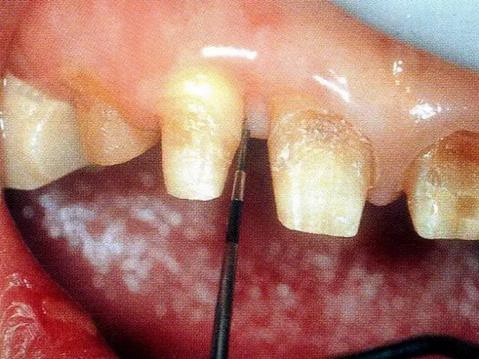

▼圖13-1 近中顎側(cè)術(shù)前牙周探診值是8mm。

▼圖13-2 將齦溝切開,盡可能保存牙齦組織的情況下做翻瓣形成。確認有根面牙結(jié)石。